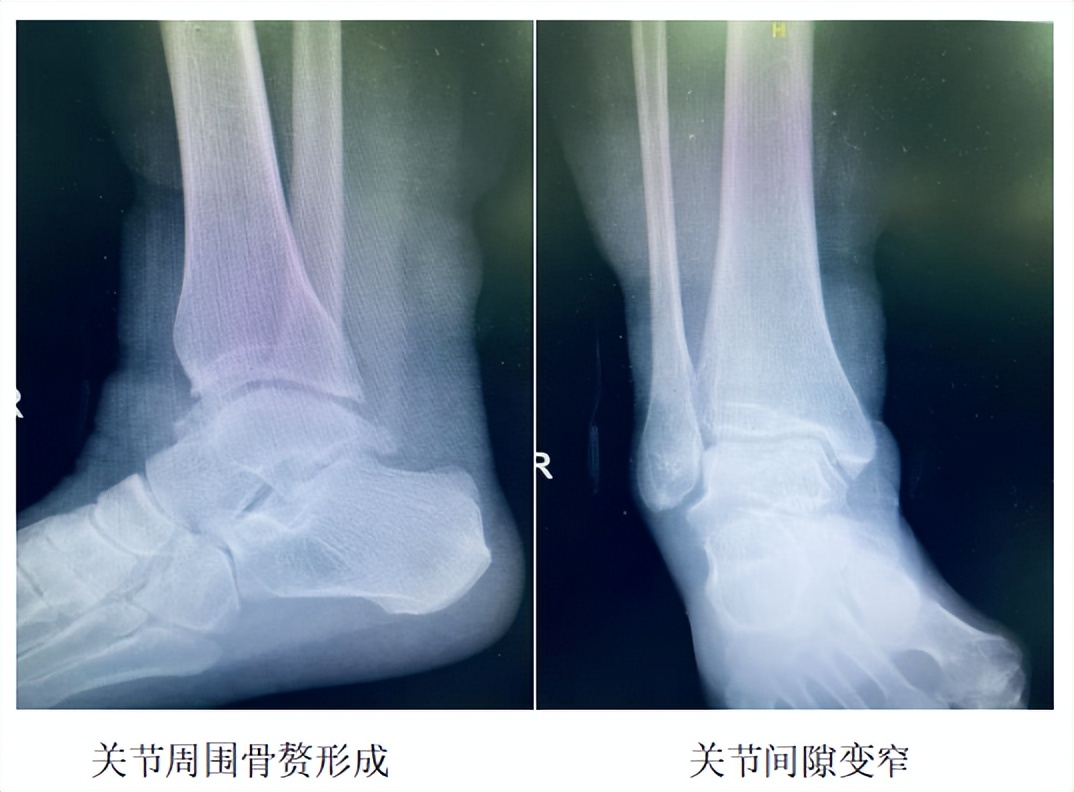

哈医大一院骨科王文波团队开展全省首例踝关节置换术

2022年3月,哈尔滨医科大学附属第一医院群力院区骨科王文波教授团队成功开展黑龙江省首例全踝关节置换手术,为一名长期受终末期踝关节骨关节炎困扰的患者,实施右侧全踝关节置换,解除患者病痛的同时,保留了踝关节的运动功能。该术式对于医院的综合实力、骨科手术团队的技术水平都要求很高,目前国内仅有几家医疗机构能够开展。

哈医大一院群力院区是黑龙江省“三高一精”示范医院,群力院区骨科也一直致力于开展国内顶尖的骨科技术。